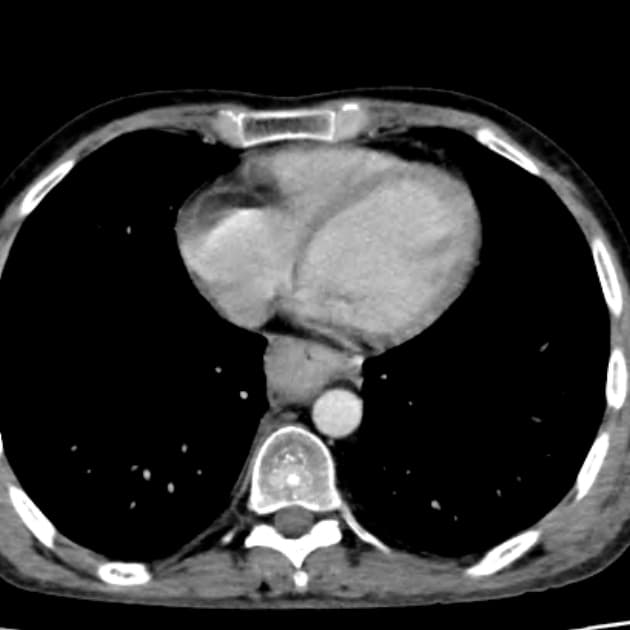

C+ arterial phase

CT•C+ arterial phase•1 / 55

Ca bệnhUng thư thực quản

Ung thư thực quản

Khó nuốt. Ung thư tế bào vảy thực quản được xác định bằng sinh thiết nội soi.

Ung thư thực quản (esophageal cancer)

Ung thư biểu mô tế bào vảy thực quản khởi phát từ biểu mô lát tầng của thực quản và là dạng tổ chức học phổ biến nhất trên toàn thế giới, đặc biệt phổ biến ở các khu vực có tỷ lệ hút thuốc và uống rượu cao. Triệu chứng điển hình bao gồm khó nuốt tiến triển, sụt cân và đau sau xương ức. Các phương tiện hình ảnh như chụp thực quản cản quang và siêu âm nội soi hỗ trợ xác định giai đoạn, trong khi CT có cản quang và PET-CT đánh giá sự di căn. Chẩn đoán sớm bằng nội soi và sinh thiết là yếu tố then chốt để điều trị triệt để bằng phẫu thuật, hóa xạ trị hoặc kết hợp cả hai.